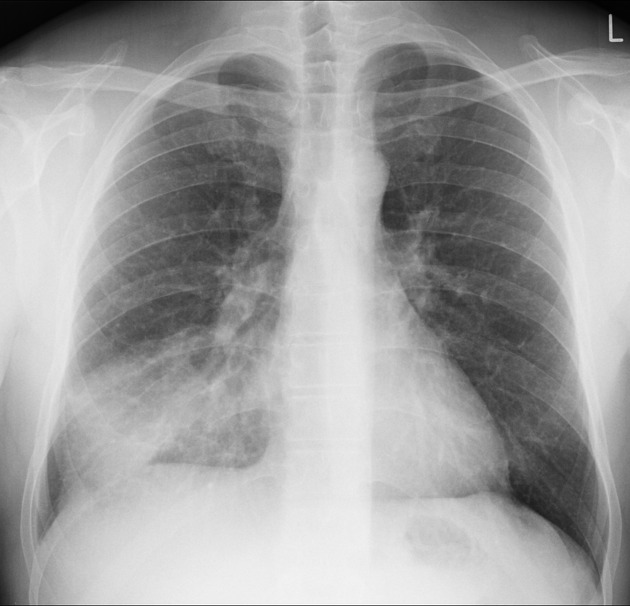

Pneumonia is an infection of the lungs caused by bacteria, viruses, or fungi. It ranges from mild to life-threatening.